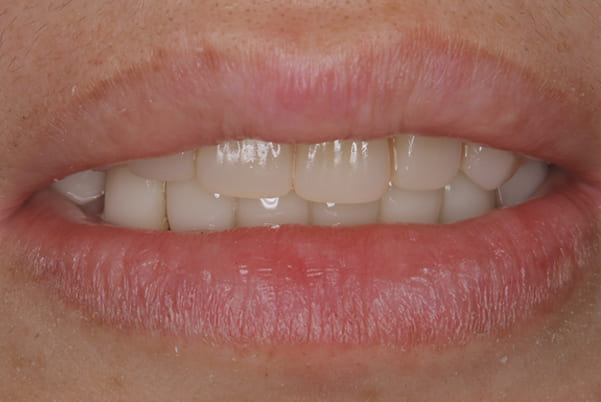

乱れたかみ合わせを治し、治療途中で見た目は患者様がご納得いく、歯の大きさ、色、形をご一緒に確認しながら入れ歯を最終的に作製しました。

-

上顎治療後

下顎治療後